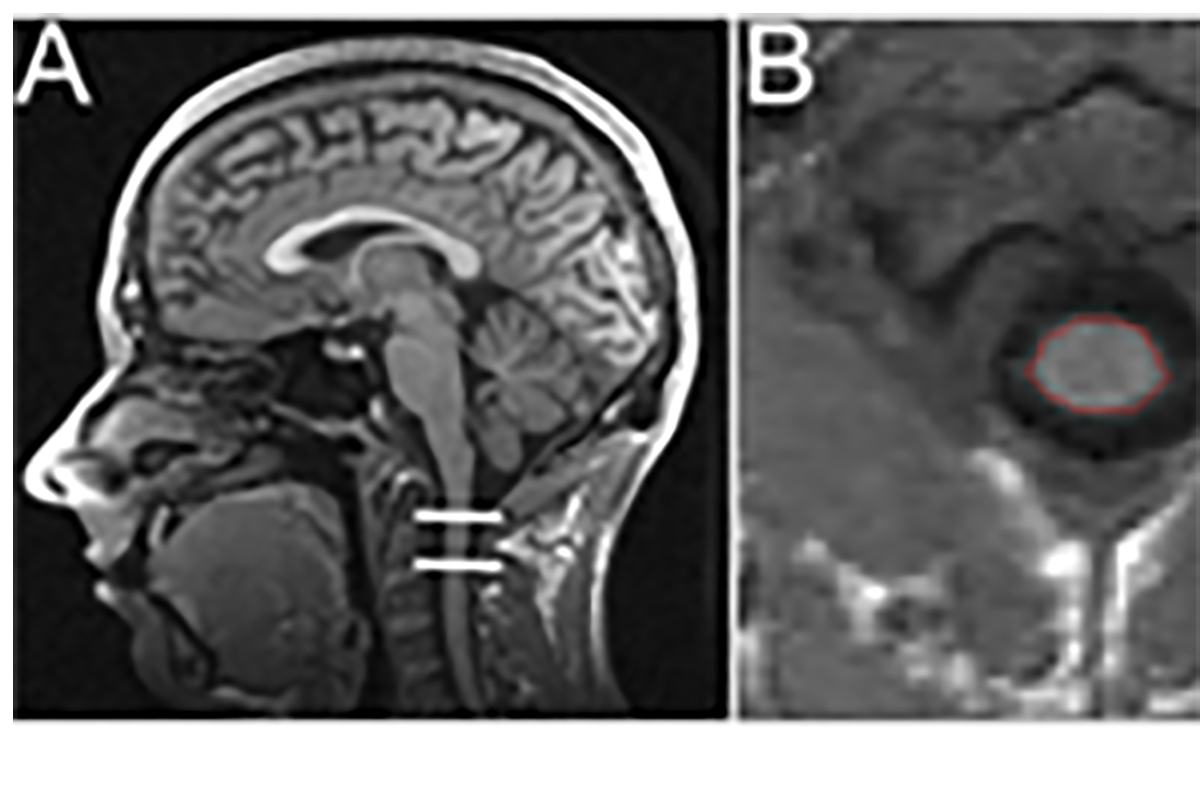

Neuro-Imaging

Zusammenhang zwischen morphometrischen Veränderungen an Gehirn bzw. Rückenmark und klinischer Wiederherstellung nach akuten Rückenmarksverletzungen.